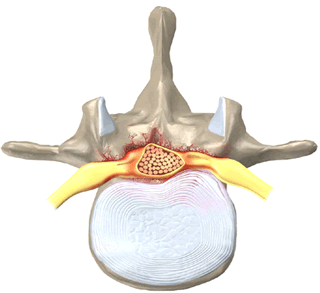

Оссификация ЗПС приводит к уменьшению передне-заднего диаметра спинномозгового канала, что приводит к стенозу спиннопозвоночного канала, сдавление спинного мозга.

- Характерный вид ЗПС в виде «перевернутой буквы Т» или «галстука-бабочки» на аксиальных срезах.

- Характерный вид ЗПС а виде «перевернутой буквы Т» или «галстука бабочки» на аксиальных изображениях.

- Сигнал обычно отличается низкой интенсивностью во всех режимах исследования

- При значительном объеме жирового компонента в костно-мозговом пространстве оссификата интенсивность сигнала может быть гиперинтесивной.